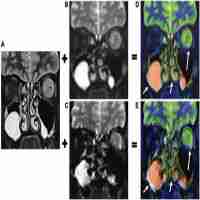

| Abstract | The signal source of apparent diffusion coefficient (ADC) changes induced by neural activity is not fully understood. To examine this issue, ADC fMRI in response to a visual stimulus was obtained in isoflurane-anesthetized cats at 9.4 T. A gradient-echo technique was used for minimizing the coupling between diffusion and background field gradients, which was experimentally confirmed. In the small b-value domain (b = 5 and 200 s/mm2), a functional ADC increase was detected at the middle of the visual cortex and at the cortical surface, which was caused mainly by an increase in cerebral blood volume (CBV) and inflow. With higher b-values (b = 200 and 1000–1200 s/mm2), a functional ADC decrease was observed in the parenchyma and also at the cortical surface. Within the parenchyma, the ADC decrease responded faster than the BOLD signal, but was not well localized to the middle of visual cortex and almost disappeared when the intravascular signal was removed with a susceptibility contrast agent, suggesting that the decrease in ADC without contrast agent was mostly of vascular origin. At the cortical surface, an average ADC decrease of 0.5% remained after injection of the contrast agent, which may have arisen from a functional reduction of the partial volume of cerebrospinal fluid. Overall, a functional ADC change of tissue origin could not be detected under our experimental conditions. |